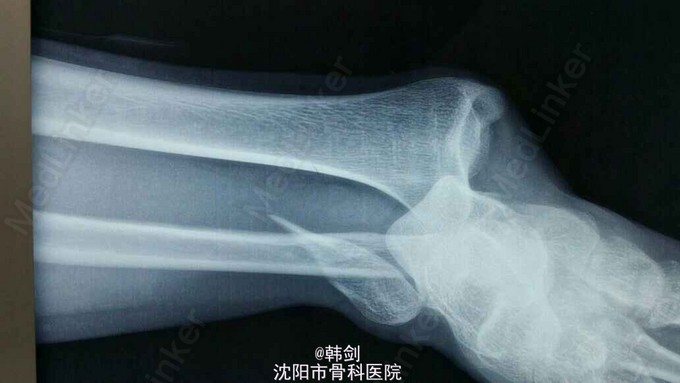

主诉:右踝外伤后肿痛,畸形,活动受限1小时。 现病史:患者于2015年9月2号晚摔伤右踝,当即肿痛,畸形,活动受限,急来诊我院,经急诊拍片,阅片及查体后以“右踝骨折”收入院。

诊断:右外踝骨折伴胫距关节脱位及内侧韧带损伤。 治疗:患者入院后,完善各项检查,行手法复位,效果不佳,于9月13日行手术治疗。三维CT为复位后拍摄。